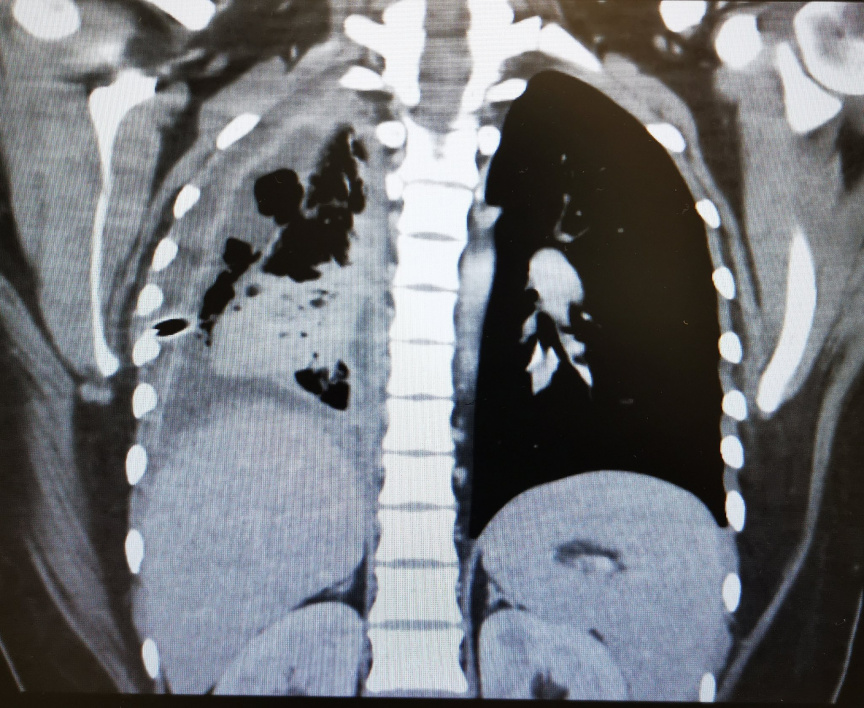

ފުއްޕާމޭގެ ބަލިތަކަށް ޚާއްސަ ޑޮކްޓަރެއް ކަމަށްވާ ޑރ. މުހައްމަދު އިސްމާއީލް ރޭ ޓްވިޓާގައި ހިއްސާ ކުރައްވާފައިވަނީ މިފަދަ ނުރައްކާތެރި ހާދިސާއެކެވެ. ފުއްޕާމޭގައި ވަރަށް ބޮޑަށް އިންފެކްޝަން އުފެދިފައި ހުރި ޒުވާން އަންހެން ކުއްޖެއްގެ ވާހަކައެވެ.

ޑރ. ވިދާޅުވިގޮތުގައި އެކުއްޖާގެ ފުއްޕާމޭގައި އިންފެކްޝަން އުފެދި ނޭވާލާ ނިޒާމުގައި ފެން އުފެދިފައި ހުރުމުން އިތުރަށް ހެދި ތަހުލީލުތަކުން ހާމަވީ ސުޕާރީ ފުކެއްގެ ސަބަބުން އެކުއްޖާގެ ފުއްޕާމޭގެ ކަނާތްފަޅި މުޅީން ބެދިފައިވާ ކަމެވެ.

ބްރޯންކޮސްކޮޕީ [ފުއްޕާމޭގައި މައްސަލައެއް ހުރިތޯ ބެލުމަށް ހޮޅި ލައްވައިގެން ހަދާ ޓެސްޓެއް] ހެދުމުން ލިބިގެންދިޔައީ ކުއްލި ހައިރާން ކަމެއް. އެކުއްޖާގެ ފުއްޕާމޭގެ ކަނާތްފަޅި ބެދިފައި ހުރީ ސުޕާރީ ފުކެއް ތާށިވެގެން.ޑރ. މުހައްމަދު އިސްމާއީލް

ޑރ. މުހައްމަދު އިސްމާއީލް ޓްވިޓާގައި ހިއްސާކުރައްވާފައިވާ ފުއްޕާމޭގެ އެކްސްރޭ